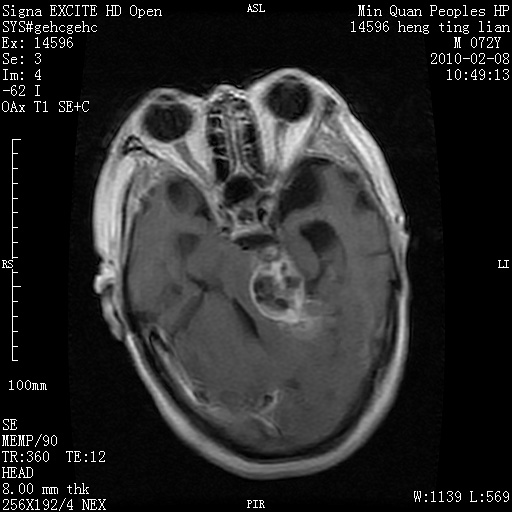

m,72,头疼,头晕两年,伴视力模糊三月,饮食呛咳两天。pe:颈部抵抗,左眼突出,左眼瞳孔约3mm,对光反射消失,双眼失明,伸舌困难,双肺呼吸音粗,心率110次/分,左上肢肌力i级,左下肢屈曲,肌张力高。现有08年2月19mri平扫及10年2月8日mri增强请会诊。ct病灶呈低密度伴散在点、片状等密度区,无明确钙化(无ct片资料可供上传)。[

脑外肿瘤,囊实性,环状不规则强化,内听道扩大,考虑神经源性肿瘤

左侧桥小脑区占位伴梗阻性脑积水----考虑 1神经鞘瘤 2室管膜瘤。

左侧桥小脑区神经鞘瘤伴梗阻性脑积水。

脑外肿瘤,病灶呈匍匐蔓延,表皮样囊肿可能性大。